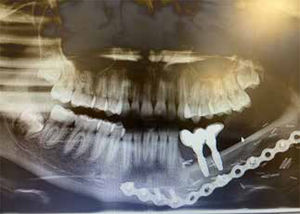

Caso clínicoPaciente 12 años, género femenino, con diagnóstico de sarcoma miofibroblástico mandibular izquierdo. Se realiza resección de tumor con reconstrucción inmediata con colgajo microvascular de fíbula, utilizando la tecnología de planificación virtual.

El protocolo utilizado para la planificación virtual en nuestro hospital, consiste en la obtención de una tomografía maxilofacial y angiotac de extremidad inferior. Los archivos en formato Digital Imaging and Communications in Medicine (DICOM) se trabajan en un software de planificación (Mimics®) y otro de diseño (3-matic®), para generar guías de corte para la fíbula y guías de corte para resección del tumor mandibular. Con los archivos en formato DICOM de la tomografía maxilofacial se genera además un biomodelo (3D), sobre el cual se contornea la placa de reconstrucción que fija el injerto microvascular a la mandíbula.

A los 4 años post reconstrucción, a la paciente se le instalaron los implantes oseointegrados, que permitieron posteriormente realizar la rehabilitación dentaria. Actualmente la paciente está libre de patología, rehabilitada desde el punto de vista funcional y estético y con una oclusión dentaria estable.